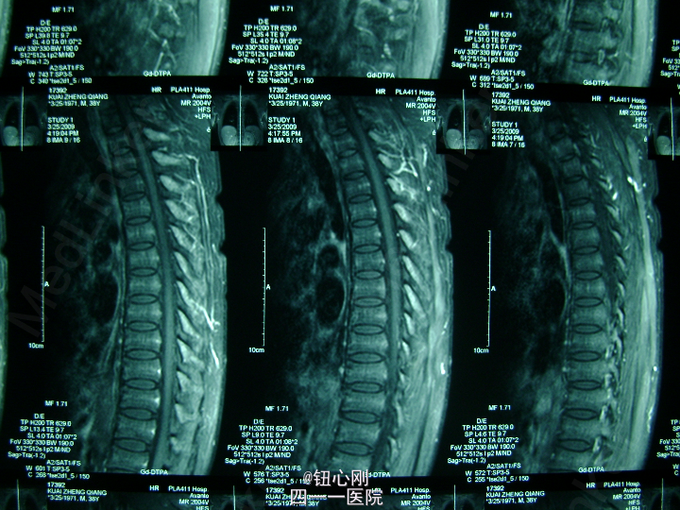

男,38岁,主诉全身多处骨关节疼痛5年。5年内身高降低5厘米,活动后全身关节疼痛加重,休息后减轻。疼痛以腰椎,全身大关节为主。既往体健,否认有肾功能不全及胃肠道病史,肝胆胰腺病史,无激素及其他特殊药物使用史。无毒物接触史。饮食正常,家族中无类似病史

查体间:略有驼背畸形,全身大关节及脊柱活动性降低,大关节处有明显叩压痛。 辅助检查:三大常规,肝肾功正常,血沉正常,各肿瘤指标正常,钙正常,血磷减低(0.44mmol/L),骨特异性碱性磷酸酶升高(99.95ng/L),PTH、CT正常,尿本周蛋白(-),血清蛋白电泳正常,无M蛋白,血皮质醇正常。 胸片,心电图,肝胆胰脾双肾B超正常。

病史特点:1、壮年男性,以全身多处骨痛为主,伴身高降低为主诉;2、体检可见:驼背畸形,脊柱及四肢大关节处活动降低,有叩压痛;3、辅助检查提示:血磷减低,血钙正常,影像学显示:全身骨骼骨质疏松改变,未见其它骨破坏。 鉴别诊断:排除骨髓瘤,转移性肿瘤,甲状旁腺亢进,肾性骨病,原发性及药物性骨质疏松 诊断:成人低磷性骨软化症 治疗:予以钙片、骨化三醇,中性磷酸盐口服